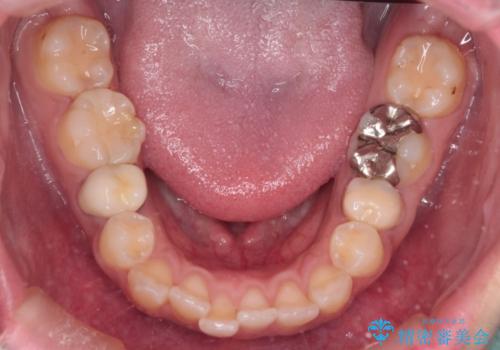

- 治療計画

抜歯によって前歯を下げるためのスペースを確保。その後、審美ワイヤー矯正を用いて、歯列全体のバランスを整えながら前歯を後方へ移動させました。治療後は、横顔のラインが整い、自然な口元になったことで、見た目も噛み合わせも改善しました。患者様からは「口元がすっきりして、自信を持って笑えるようになった」と喜びの声をいただきました。